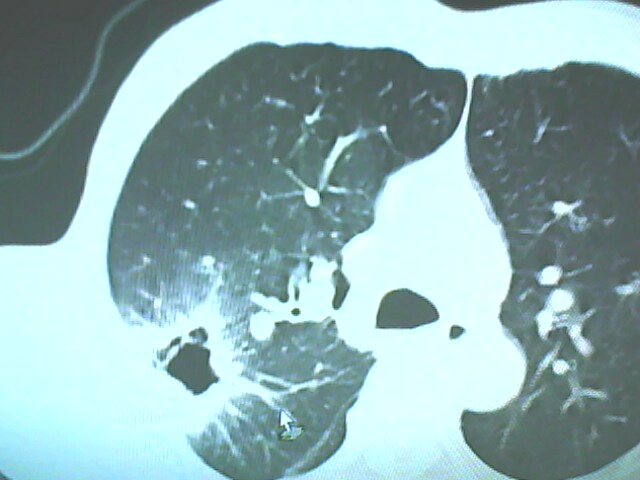

患者,男,66岁,以咳嗽、咳痰伴胸痛来就诊。

胸片提示右上肺占位病变。请各位老师看看ct。

考虑癌性空洞可能性大,空洞内壁不规则,病灶周围模糊,分叶、有毛刺

空洞内壁不规则,病灶周围模糊,分叶、毛刺呈日光放射状,突然截断,支持考虑癌性空洞

考虑癌性空洞可能性大,内壁不规则,洞壁薄厚不均呈结节状突起,边缘模糊,分叶,毛刺

右上肺后段肺癌:

典型癌性空洞(偏心性,壁厚薄不均,内壁不光整),周围毛刺较僵硬,且有刺突征和血管聚集征